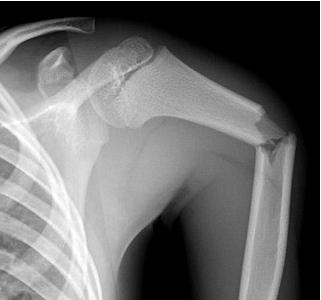

ПІСЛЯ АВТОМОБІЛЬНОЇ АВАРІЇ НА РЕНТГЕНОГРАМІ ВИЯВЛЕНО ПЕРЕЛОМ КІСТКИ В ДІЛЯНЦІ ХІРУРГІЧНОЇ ШИЙКИ. ЯКА КІСТКА МАЄ ТАКУ ШИЙКУ?

варіанти відповідей

РОЗПІЗНАЙТЕ НА РЕНТГЕНОГРАМІ СУГЛОБ, ЩО МАЄ МІЛКУ СУГЛОБОВУ ЗАПАДИНУ І СКРІПЛЕНИЙ ПЕРЕВАЖНО М'ЯЗАМИ, ТОМУ ТУТ ВІДНОСНО ЧАСТО БУВАЮТЬ ВИВИХИ.

ХІРУРГІЧНОЇ ШИЙКИ HUMERUS

АНАТОМІЧНОЇ ШИЙКИ HUMERUS